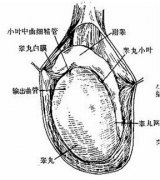

都市男性睾丸生精功能障碍出现的病因

生精功能障碍要做哪些检查

生精功能障碍有哪些危害?

生精功能异常会出现什么症状?

生精功能障碍要做哪些检查?